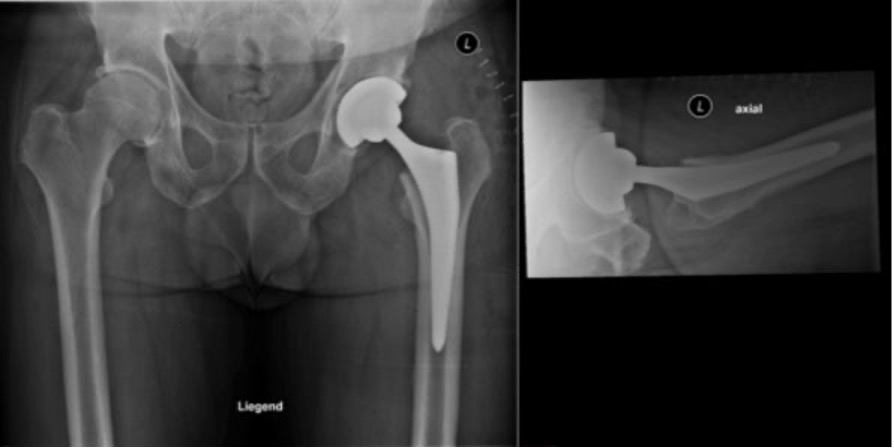

Postoperatives Röntgenbild nach einerHüfttotalendoprothese (links)